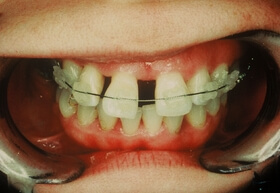

A fogágybetegség kezelése után a beteg fogszabályozó készüléket kap az esztétikai eltérés korrekciójára

A kezelés végén a fogszabályozó készülék eltávolítása előtt

A végeredmény, a frontfogak a belső oldalon összesínezve